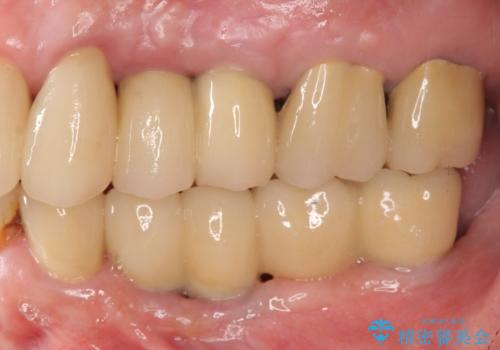

虫歯による歯の喪失 インプラントによる咬合機能回復

複雑な問題点に対する明確な治療目標を立てることで、最終的に長い予後を期待できる治療を達成することができます。